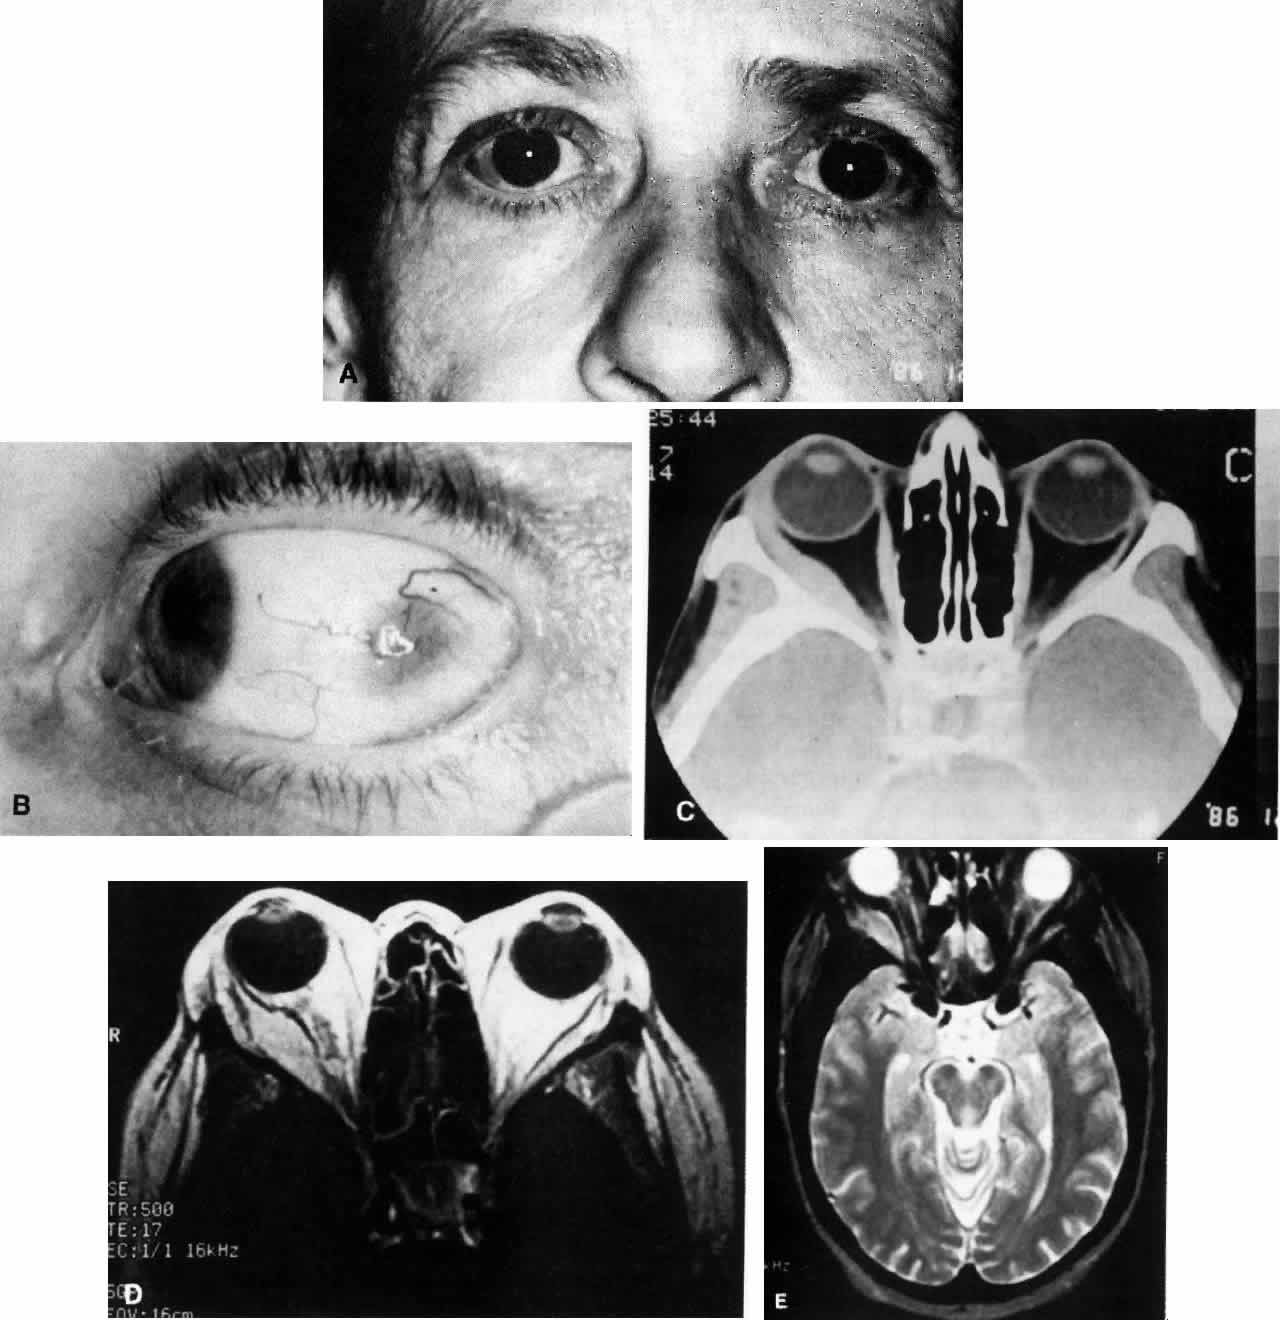

Fig. 1. A. A 36-year-old woman presented with right-sided pain and proptosis occurring over a several-day period. Externally the eye is quiet and does not appear inflamed. The patient had no complaints of diplopia or other visual disturbances. Tissue obtained at biopsy demonstrated idiopathic orbital inflammation. B. Axial CT image from the same patient demonstrates bilateral orbital masses located laterally in the orbits. Note that masses are ill defined and do not appear to have a capsule. The masses are molded to the bony orbital walls without evidence of any bony irregularities. C. Coronal CT image from the patient again shows the presence of bilateral orbital masses apparently involving the lateral rectus muscles.

Fig. 2. A 54-year-old woman presented with acute orbital inflammation demonstrating significant proptosis and inflammatory signs involving the right orbit. In addition to severe pain, the patient had diplopia secondary to orbital edema and inflammation.

Fig. 3. A. A 62-year-old woman presented with diplopia and minimal right-sided proptosis. B. Enlarged lateral rectus muscle is visible subconjunctivally. C. Axial CT image confirms myositis involving the lateral rectus muscle. Note that the muscle as well as its tendon are involved in the inflammatory process in contrast to muscle involvement in thyroid-related orbital disease. D. T1-weighted MRI image demonstrating myositis involving the lateral rectus muscle. In this case the muscle belly is enlarged but the tendon appears relatively unaffected. E. T2 weighted MRI image of orbital myositis showing little difference in appearance of muscle between T1- and T2-weighted images.

The most important ancillary studies to be performed in evaluating idiopathic orbital inflammation are orbital ultrasonography and CT (see Figs. 1 AND 3).3–6,11,49,77–80 Ultrasonography is helpful for demonstrating exudative retinal detachment, edema in Tenon's fascia, enlargement and “doubling” of the optic nerve shadow (the “T” sign), enlargement of the extraocular muscles, and the presence of a distinct orbital mass.4,77,81,82 CT may be more useful in establishing the diagnosis.18,20,65,67 As with ultrasonography it will demonstrate the extent of anterior orbital involvement, including thickening of the posterior sclera and retinal detachment, but it is more useful in demonstrating the entire extent of the extraocular muscle, optic nerve, posterior orbit, and involvement of the cavernous sinus. In addition, it will show if there is any associated sinus disease or bony erosion that would suggest a neoplastic process or one of the necrotizing vasculitides such as Wegener's granulomatosis. Testing for anticytoplasmic autoantibodies, which are highly specific for Wegener's granulomatosis, will also help to differentiate this entity from idiopathic causes of scleritis and idiopathic orbital inflammation.83

Other studies that may be useful include MRI, orbital venography, cerebrospinal fluid analysis, and measurement of the erythrocyte sedimentation rate.6,58,84 MRI is certainly helpful for clarifying the extent of any intracranial disease. It may also be helpful for differentiating focal orbital inflammation masquerading as a tumor of the orbit, extraocular muscles, or lacrimal gland from a true neoplastic process. Orbital venography may be helpful in demonstrating vascular deformities that are seen in the Tolosa-Hunt syndrome and occasionally in other forms of inflammatory orbital inflammation.58 The erythrocyte sedimentation rate may be elevated in cases of orbital inflammation, but this should bring to mind the possibility of a concurrent systemic disease such as one of the collagen vascular diseases. Cerebrospinal fluid pleocytosis due to meningeal irritation has also been reported.6 Gallium scanning has also been used to image orbital “pseudotumor” to differentiate it from other entities involving the orbit.85